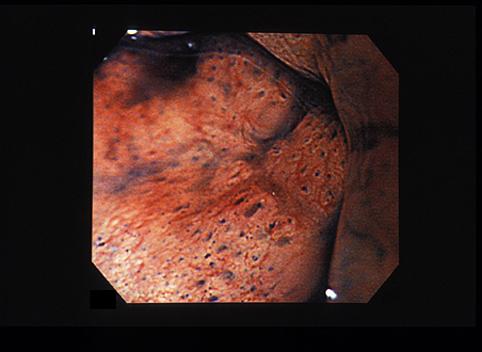

A case of ectopic gastric mucosa which developed in the rectum.

[ Image ID:7690 ]

Tumor-like lesions/ectopic mucosa

Large intestine(Colon)/Rectum

Endoscopy

10 - 14